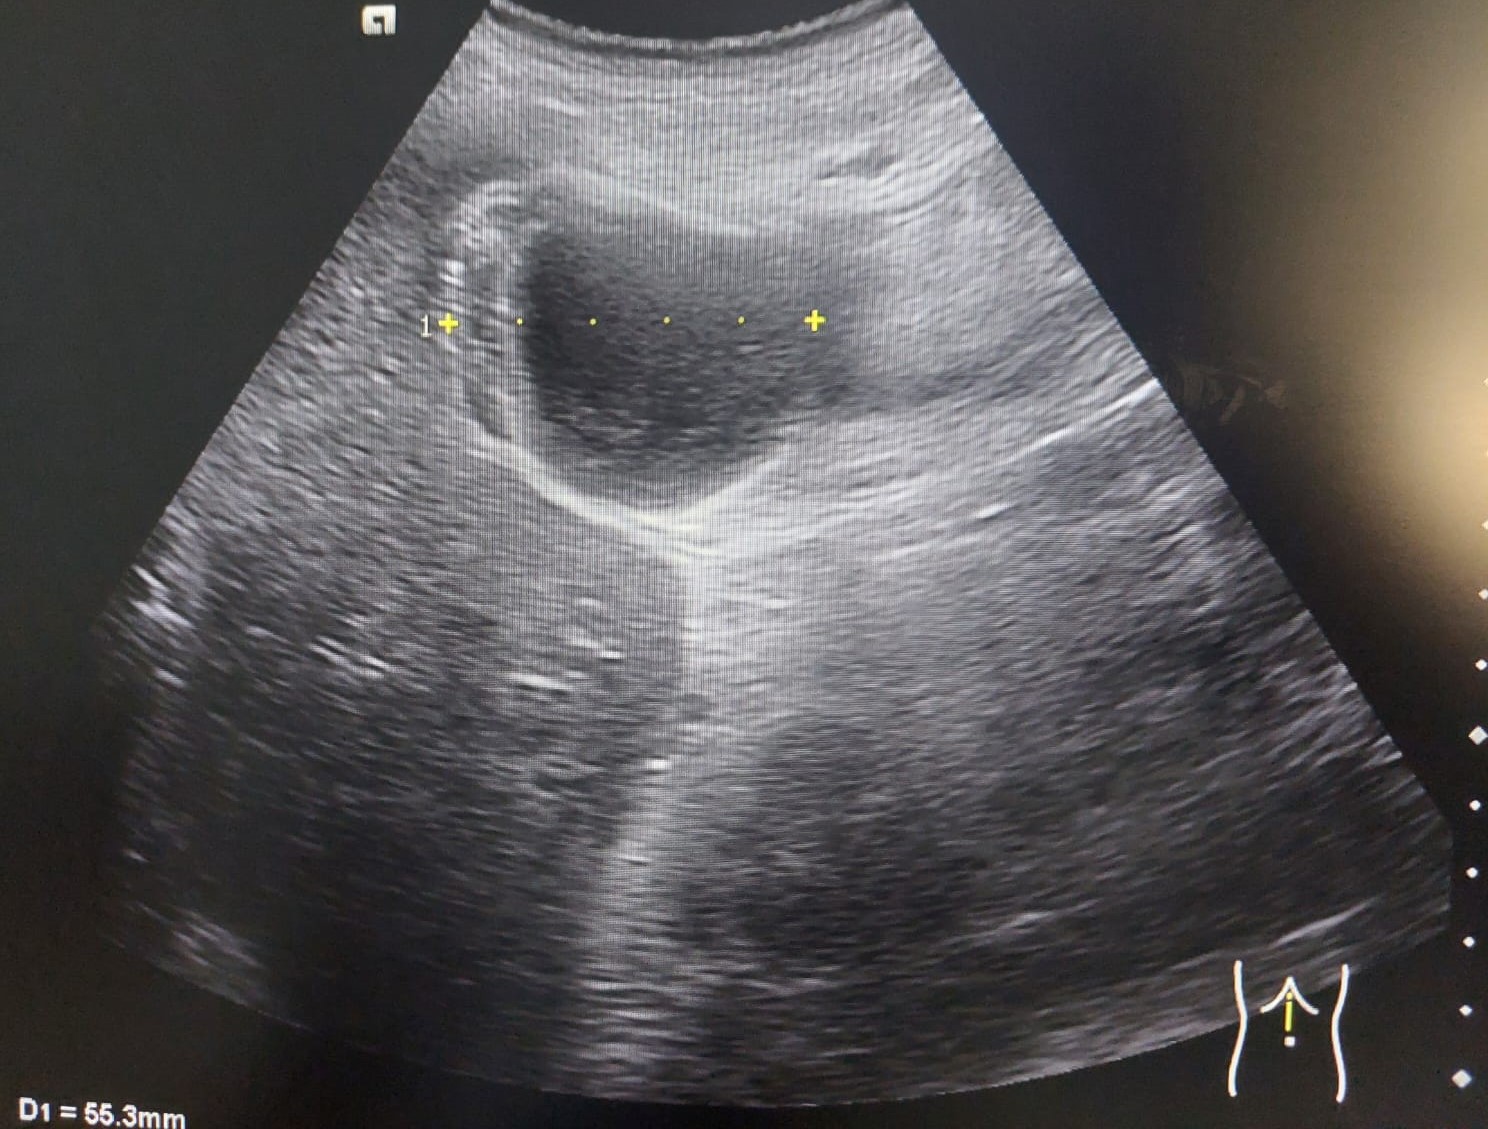

Se realiza una ecografía clínica abdominal en la que destaca un engrosamiento de la pared anterior de la vesícula biliar, sin imágenes hiperecogénicas en su interior. Parénquima hepático y riñón derecho con morfología y ecoestructura normal.

Se deriva a cirugía que solicita ecografía reglada informándola como vesícula biliar distendida, con engrosamiento marcado y limitado a la pared del fundus vesicular asociado a barro biliar. Hallazgos no concluyentes para colecistitis aguda, y podría estar en relación con adenomiomatosis del fundus asociado a barro biliar, o menos probable colecistitis subaguda.